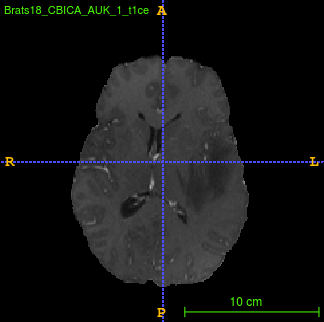

Segmentation of brain tumor from magnetic resonance imaging (MRI) is a vital process to improve diagnosis, treatment planning and to study the difference between subjects with tumor and healthy subjects. In this paper, we exploit a convolutional neural network (CNN) with hypercolumn technique to segment tumor from healthy brain tissue. Hypercolumn is the concatenation of a set of vectors which form by extracting convolutional features from multiple layers. Proposed model integrates batch normalization (BN) approach with hypercolumn. BN layers help to alleviate the internal covariate shift during stochastic gradient descent (SGD) training by zero-mean and unit variance of each mini-batch. Survival Prediction is done by first extracting features(Geometric, Fractal, and Histogram) from the segmented brain tumor data. Then, the number of days of overall survival is predicted by implementing regression on the extracted features using an artificial neural network (ANN). Our model achieves a mean dice score of 89.78%, 82.53% and 76.54% for the whole tumor, tumor core and enhancing tumor respectively in segmentation task and 67.90% in overall survival prediction task with the validation set of BraTS 2018 challenge. It obtains a mean dice accuracy of 87.315%, 77.04% and 70.22% for the whole tumor, tumor core and enhancing tumor respectively in the segmentation task and a 46.80% in overall survival prediction task in the BraTS 2018 test data set.